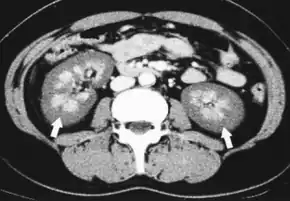

Diagnosis

While the only diagnostic "gold standard" mechanism of diagnosis en vivo is via kidney biopsy, the clinical conditions and blood clotting disorder often associated with this disease may make it impractical in a clinical setting. Alternatively, it is diagnosed clinically, or at autopsy, with some authors suggesting diagnosis by contrast enhanced CT.[19]